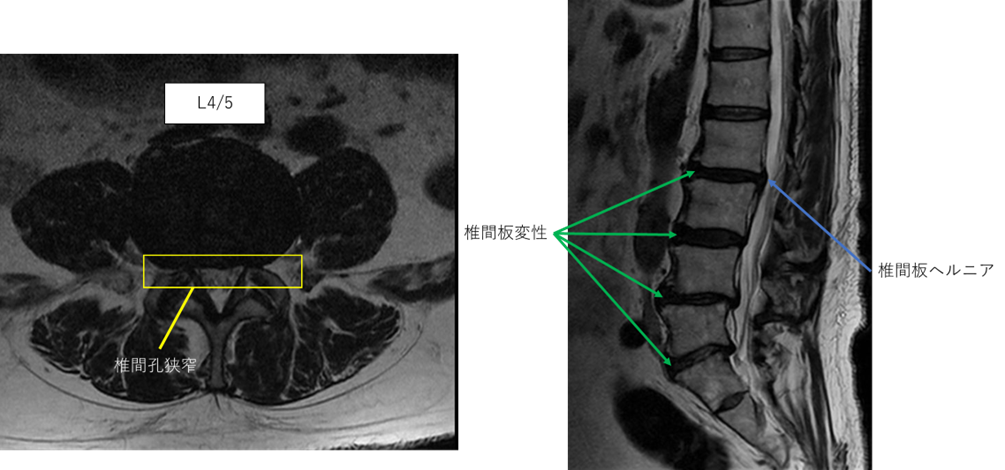

L2/3: 椎間板ヘルニア、椎間板変性症

L3/4: 椎間板変性症

L4/5: 椎間板変性症、両椎間孔狭窄

L5/S: 椎間板変性症、両椎間孔狭窄

L2/3、3/4、4/5、5/sに

椎間板ヘルニア、椎間板変性症、両椎間孔狭窄 を認め、主症状の原因の可能性が高い。